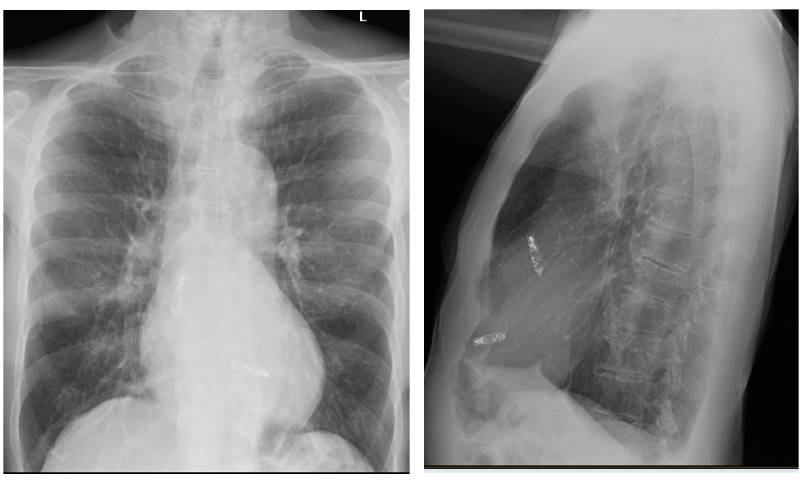

Chest x-ray with pacemaker

A chest X-ray from a patient who had a dual chamber leadless pacemaker implanted.